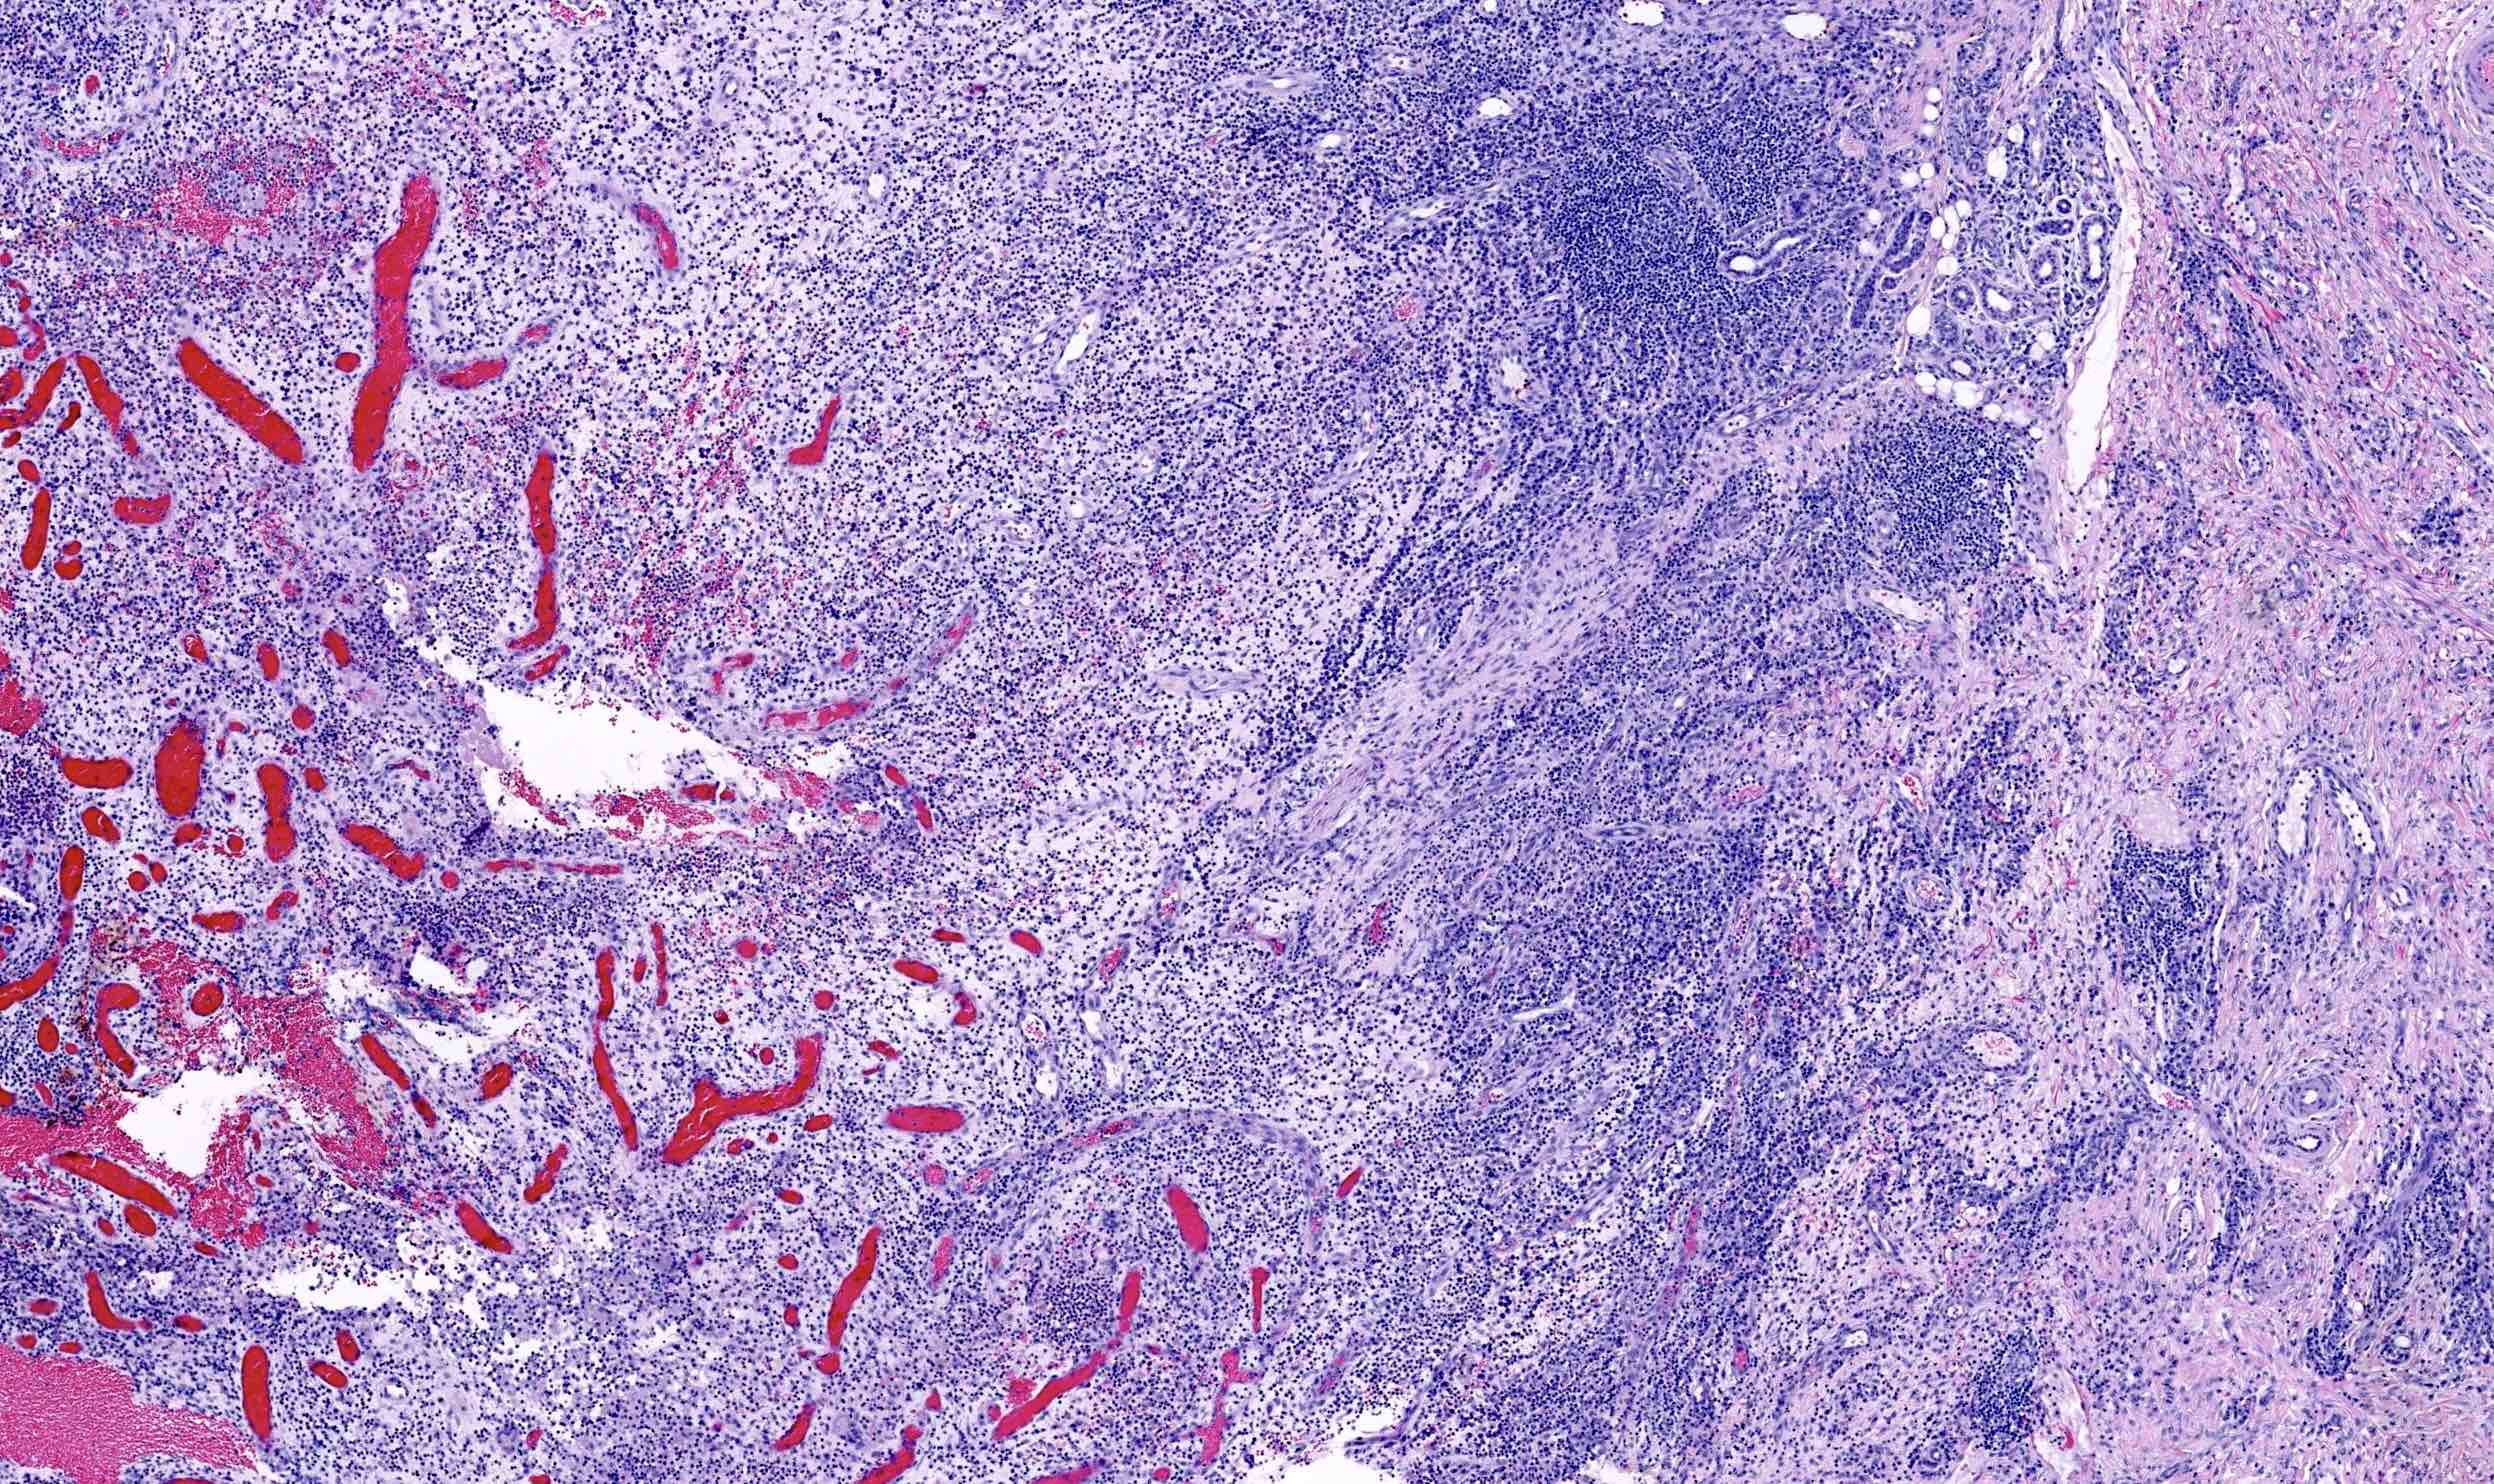

Microscopic (histologic) description

- In early lesions: follicular hyperkeratosis, hyperplasia of follicular epithelium and perifolliculitis (Br J Dermatol 2011;164:367)

- Dermal mixed inflammatory cell infiltrate, sometimes extending into the subcutis (Br J Dermatol 1990;122:763)

- Neutrophilic abscesses, which may connect with squamous epithelium lined cysts and sinus tracts that extend to the skin surface (Br J Dermatol 1990;122:763)

- Cysts and sinus tracts contain laminated keratin and occasional hair follicles (Br J Dermatol 1990;122:763)

- Granulation tissue with occasional foreign body giant cells present in ~25% of cases (Histopathology 1993;23:111)

- Inflammation involves apocrine glands in a minority of cases (J Am Acad Dermatol 1996;34:994)

- Dense fibrosis surrounding areas of follicular rupture

Microscopic (histologic) images